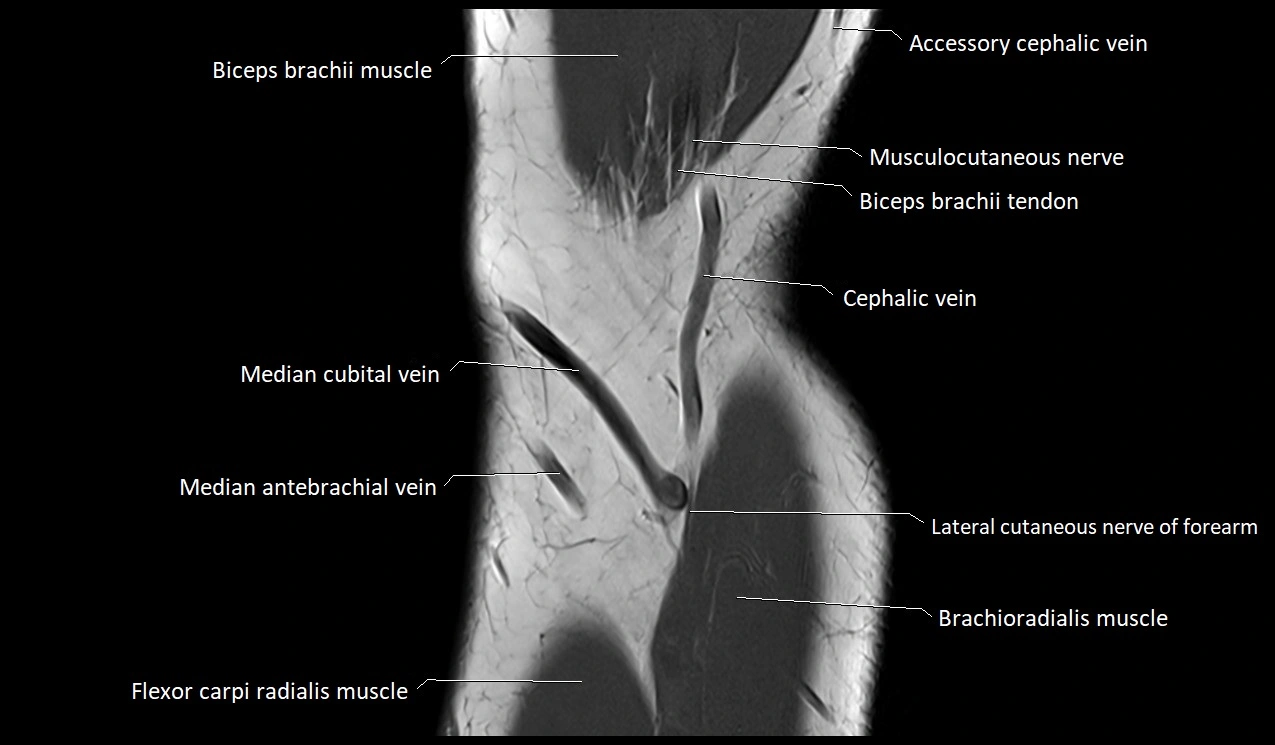

MRI image

image